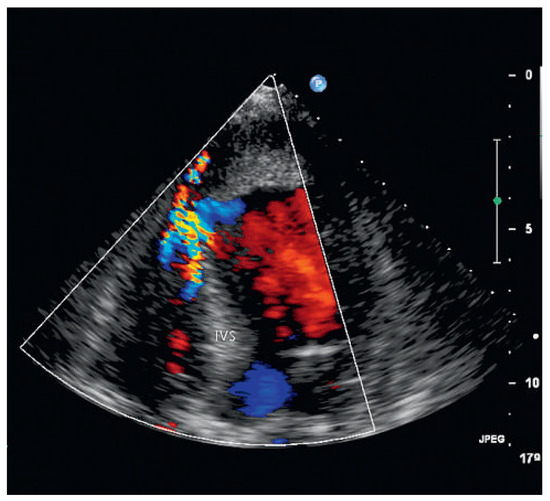

Since the first description of the athlete’s heart in 1899 by Henschen and Darling, the knowledge on cardiovascular adaptations to exercise conditioning h as expanded considerably. There is an ongoing debate about the true nature of the athlete’s hea...